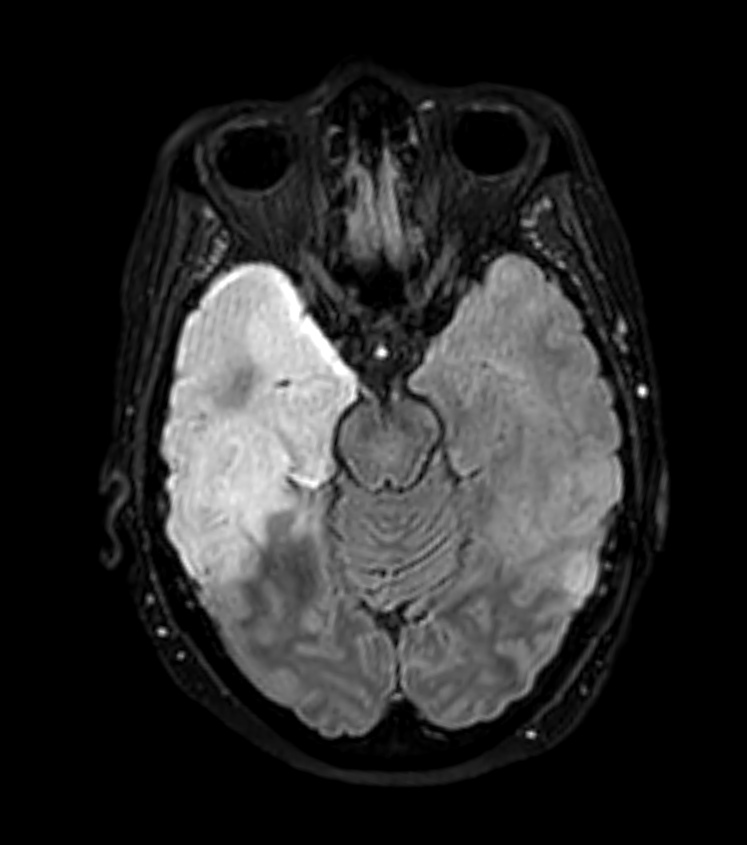

- MRI findings (more sensitive than CT):

- T2/FLAIR: hyperintense signal in affected regions

- DWI: restricted diffusion in acute phase

- SWI: petechial haemorrhages

- Typical distribution:

- Asymmetric involvement of temporal lobes (95% of cases)

- Frontal lobe involvement (80% of cases)

- Insular cortex, cingulate gyrus may be affected

- Sparing of basal ganglia

- 60-year-old patient presented with expressive dysphasia.

- MRI showed diffuse patchy cortical, white matter and ganglionic hyperintensity.

- On follow-up, hyperintensity involving most of the left temporal lobe resolved while marked hyperintensity developed in the right temporal lobe.

- Despite being repeatly negative on CSF, brain biopsy reavealed an HSV encephalitis.